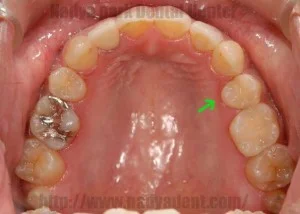

古い金属の詰め物をすべて除去し、セラミック等の白い材料でやりかえた事例

噛み合わせの調整後、金属除去、型採り、装着のステップで実施 / セラミック1本 ¥80,000~(税別) + 型取り ¥3,000(税別) (※本症例では右下6・左下6にセラミック、右下7・左下7に保険内CR、その他小金属に保険内修復を適用)リスク・副作用:治療後に一時的なしみや違和感が生じる可能性。過度な衝撃による破損や、経年劣化による変色・脱離のリスク。